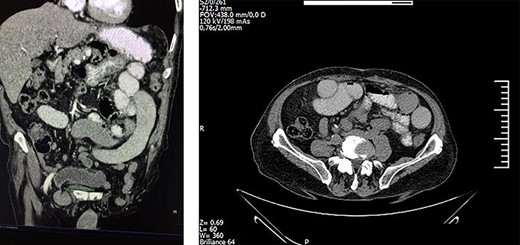

Laboratory examination revealed increased levels of C-reactive protein, LDH and neutrophils. Subsequent computed tomography (CT) and magnetic resonance imaging (MRI) of the abdomen and the pelvis indicated bowel obstruction of the sigmoid colon and obstruction of several loops of the small intestine as well (Fig 1). Herein, the patient underwent emergency laparotomy 2 h after he was initially assessed by the surgical team.

Surgeons performed high McEvedy’s approach and identified a small knuckle of gangrenous bowel strangulated in the right femoral hernia, while the left one included a small part of the sigmoid colon, which was still viable (Fig 2). The ischemic bowel loops were dissected off, and an anastomosis was immediately performed via a stapler device.

Strangulated bilateral femoral hernia; the right hernia included gangrenous loops of the ileum and the left one included a small part of the sigmoid colon.